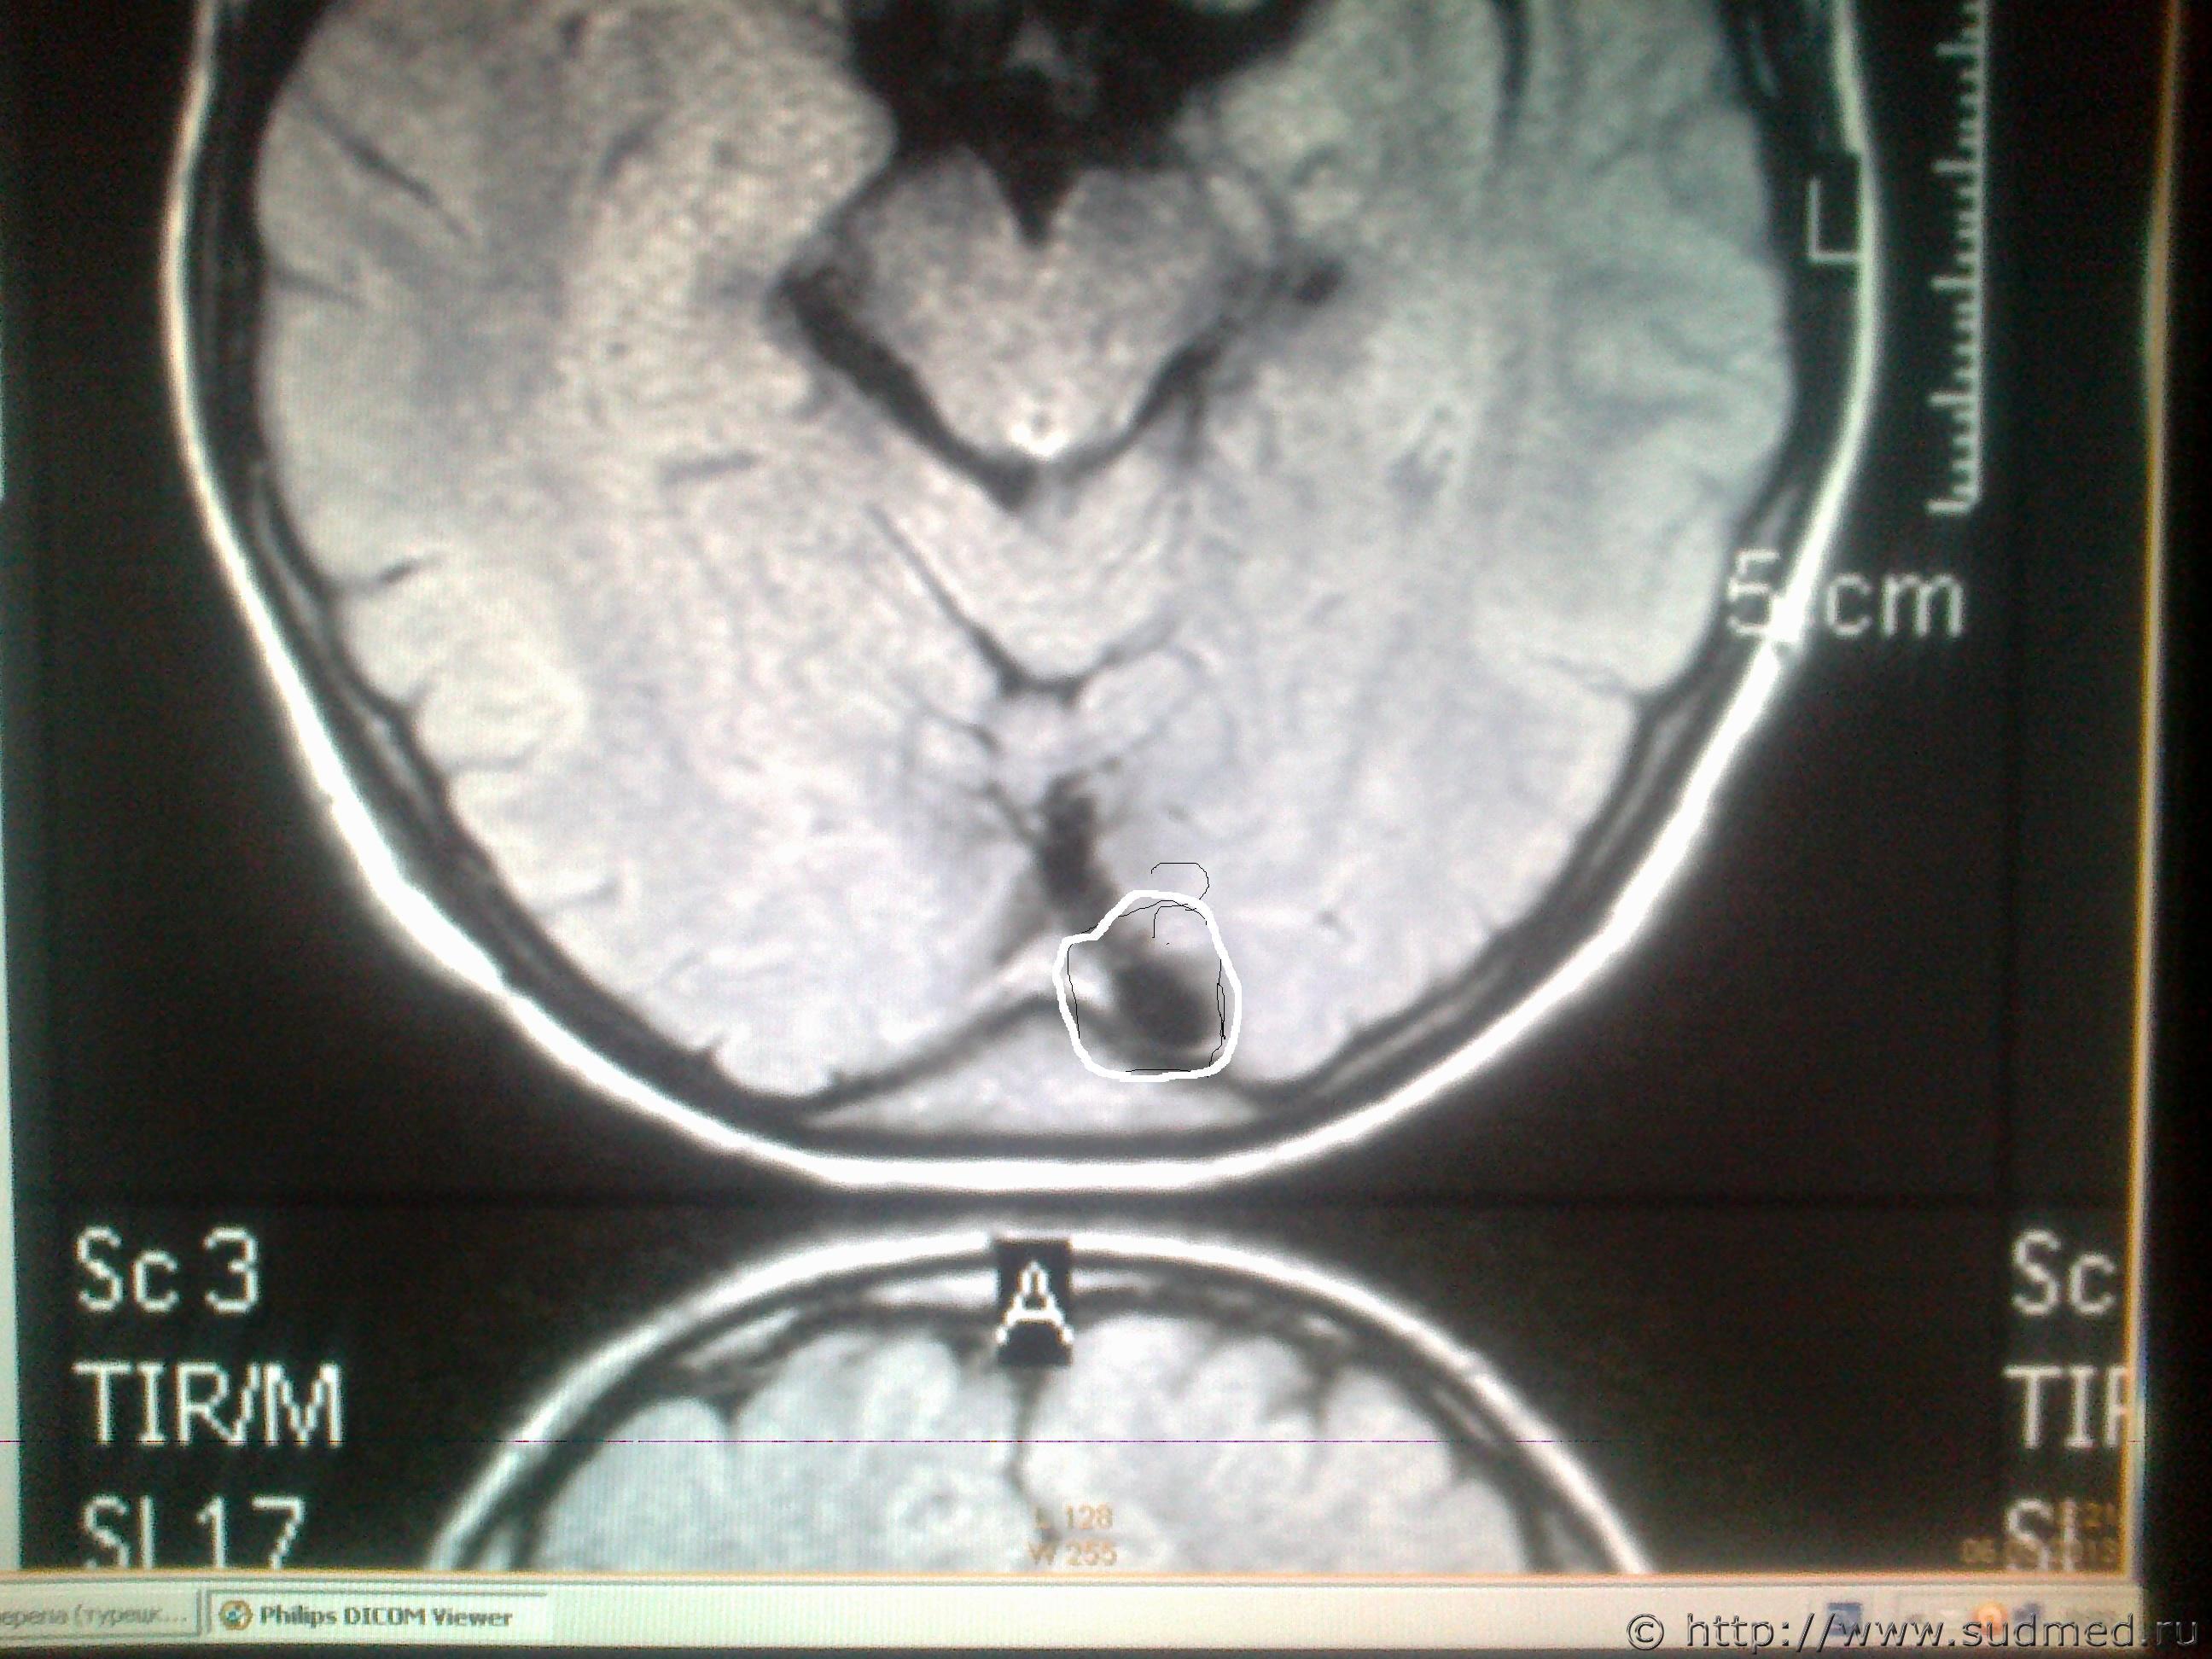

ув. специалисты! Мне оч. хочется узнать ваше мнение, что показано на мрт снимках в мозгу и на костной ткани, интересующие места обведены. Есть ли трещины на костях черепа или это шов и что значит чёрное- белое пятно на снимке мозга?

Светичок! Надо показать сами эти снимки специалисту по МРТ (на пленке и/или на электронном носителе. На эл.носителе даже лучше, т.к. на пленке могут быть распечатаны, к примеру, 30 сканов, а, фактически, их 150 было выполнено и все они могут быть представлены Вам на диске или на флешке). Присланное Вами хуже по качеству, чем снимки, которые есть фактически и, на этом форуме, насколько мне известно, нет врачей имеющих сертификат по специальности"Рентгенология" и дополнительную специальную подготовку по ядерно-магнито-резонансной томографии. Поищите какой-нибудь форум рентгенологов, вероятно, там смогут дать более компетентные комментарии. Насколько я разбираюсь в МРТ (немножко): на снимках №1, 2 и 3 - вероятнее всего, ликворная киста. Возможно, это вариант развития, возможно, след от давно регрессировавшей (прошедшей, рассосавшейся) гематомы. В любом случае, даже если это изменение имеет посттравматическое происхождение, то травма была давно (месяцы или годы назад), на что указывает отсутствие признаков внутричерепной гематомы, перифокального отека вещества головного мозга. Только по этим снимкам ни один специалист не сможет серьезно и аргументированно доказать, что это: 1.именно последствие травмы и ни что другое, 2.точно установить дату этой предполагаемой травмы. (Просьба не путать специалиста с шарлатаном, который, "все что угодно за ваши деньги" - в суде такое "заключение" окажется несостоятельным). На снимках №4 и 5 - шов между затылочной и теменными костями, №6 - каналы диплоэтических вен (вены, проходящие сквозь кости черепа. Они извитые, а перелом, в такой проекции выглядит как прямая линия, перпендикулярно и косо-перпендикулярно пересекающая кость свода черепа). МРТ - неоптимальный метод для оценки состояния костей свода черепа (МРТ - великолепный метод для оценки состояния мягких тканей). Гораздо лучше - обычная рентгенография костей свода черепа. Желательно,сделанная на современном цифровом рентгеновском аппарате. Желательно - полипозиционная (т.е. не только стандартные снимки в прямой и одной из боковых проекций, а, в данном случае - прямая проекция,правая и левая боковые проекции, контактная рентгенограмма затылочной кости и, возможно, снимок с выведением места предполагаемого перелома в краеобразующую зону. Тогда на 100% будет понятно,что это такое. Вероятно, на 100% будет понятно уже на стадии рентгенограмм в прямой и боковых проекциях. Грамотный рентгенолог знает все это лучше, чем я тут написал). Можно, конечно, сделать мультиспиральную компьютерную томографию /МСКТ/ в костном режиме с 3-D реформацией изображения,однако, лучевая нагрузка будет больше, а информативность - сопоставимая. Если в итоге найдется что-то похожее на посттраматические изменения, то нужно будет провести исследование всех рентгенограмм, которые выполнялись непосредственно после конкретной травмы, если когда-то до неё делались рентгенограммы, МРТ, КТ головы - их тоже. Это уже задача судебно-медицинской экспертизы. + будут учитываться данные медицинских карт и прочие документы о лечении после этой травмы, о состоянии здоровья до неё и т.п., т.к. перелом кости/костей свода черепа, внутричерепная гематома протекают с весьма выраженной клинической симптоматикой (от чего-то "легкого" и похожего на "сотрясение головного мозга" до тяжелых невропатологических проблем).